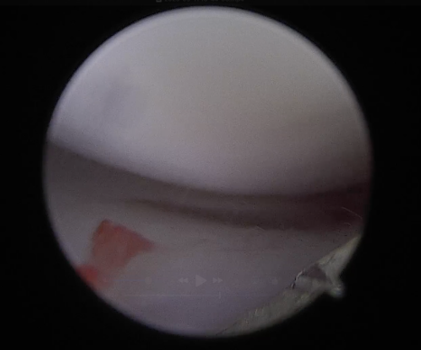

.png)

후방 십자인대 부분 손상 및 염증성 변화 확인

손상되지 않은 반월판 확인 된 모습